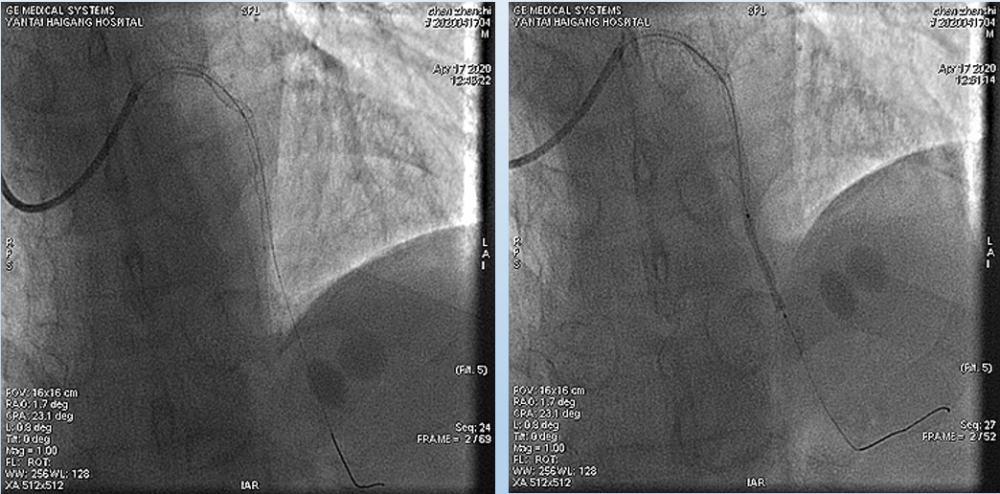

4月17日介入治疗结果如图所示:

文章插图

根据造影结果及患者病情 , 决定优先处理前降支病变 , 择期处理右冠;

分别送导丝至前降支及第一对角支 , 送2.0mm×15mm预扩球囊对病变部位进行充分预扩张处理 。

于前降支中段、左主干-前降支近段依次置入PROMUS ELement 2.5mm×38mm、PROMUS Element3.0mm×38mm支架共2枚 。

复查造影前降支支架以远可见99%局限狭窄 , 于前降支远段置入Firebird 22.5mm×23mm支架1枚 , 并给予后扩张 。